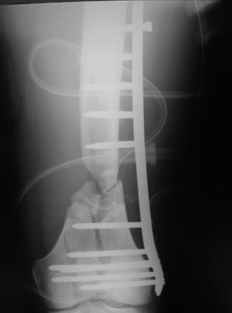

Look what we would have done.

|